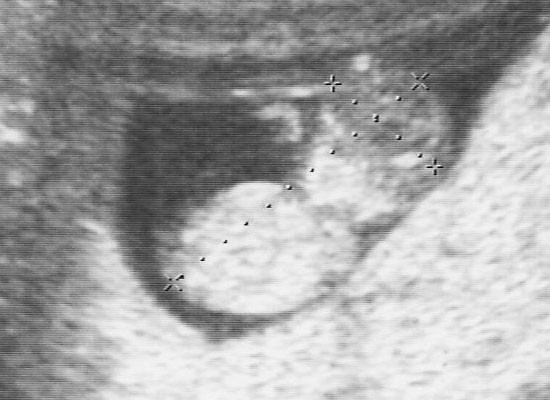

『胎のうがうっすらと確認出来る程度なんで、まだはっきりとわからない』と言われてたんですね。

しかしとりあえず、丸い粒は見えて着床してるって事はわかったんで、旦那には『育つかどうかわからんけどとりあえず出来てるっぽい』と説明しときました。

胎のうやら、心音は結構早めに確認出来てたんですけどね。

内視鏡写真は毎度いただけます。

中期に入ったら4D写真・ビデオ録画もついてきますー。